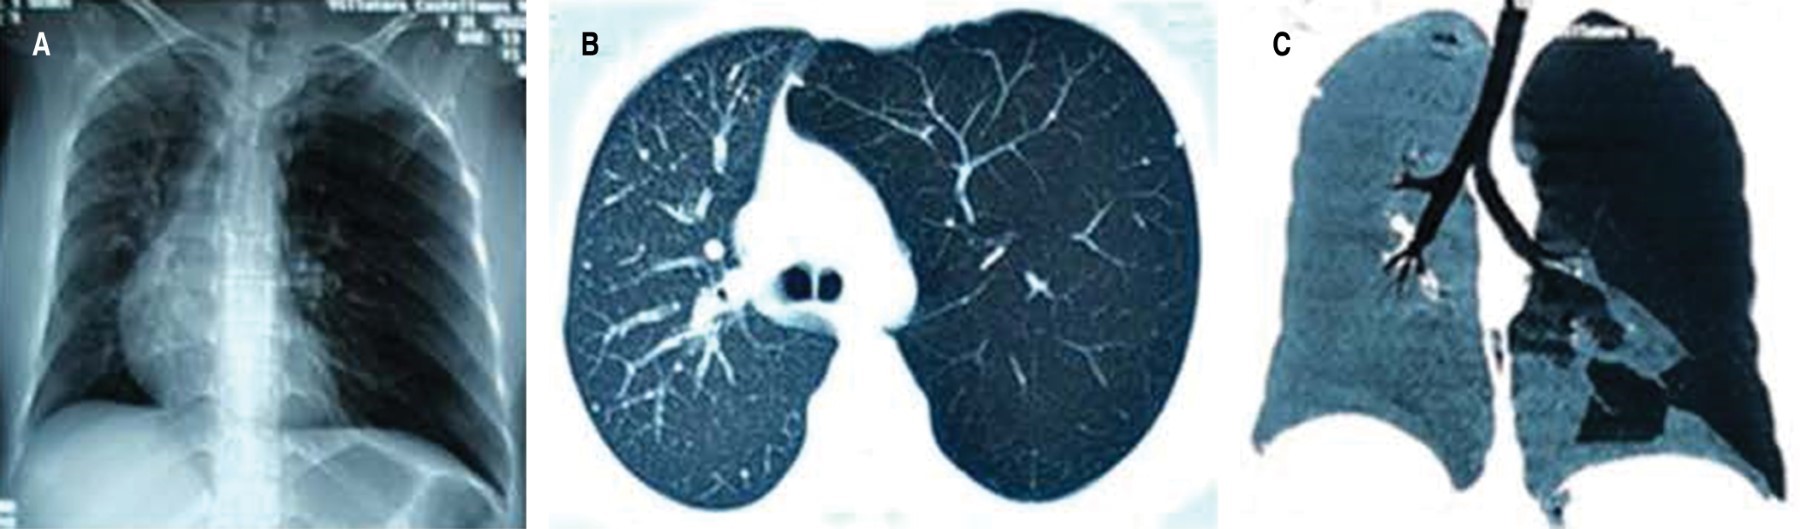

Chest X-ray showed left lung overdistended, displacing the mediastinum to the right and hyperlucent; computed axial tomography (CT) showed, in addition, anomalous distribution of the pulmonary vasculature with areas of hypoperfusion of variable distribution (Figure 1).

A mild chest pain prompted consultation and radiography showed a hyperlucent left lung. It is most commonly diagnosed in infancy, typically occurring in children under eight years of age, before the lung has completed lung development and maturation.5 It may run asymptomatically into adulthood, present with usually asymptomatic spontaneous pneumothorax,2 or as a rare emergency condition,3 as calcified bullae6 and with placental transfiguration of the lung parenchyma.7 The patient's chest X-ray and CT scan showed hyperlucent segmental lung with altered vascularity, which is usually described by other authors as unilateral or lobar pulmonary hyperclarity, associated with air trapping of the hyperlucent lung during expiration.2,5,8 In order to rule out the differential diagnosis of pulmonary thromboembolism, angiotomography was requested, which showed anatomical abnormalities of the left pulmonary artery with a smaller caliber and decreased flow. The spirometric pattern showed restrictive process. Pulmonary scintigraphy was not performed that could show decreased ventilation of the pathologic lung secondary to emphysematous changes and a marked decrease in perfusion, as a consequence of the reduced caliber of the pulmonary artery.5,8 Therefore, diagnostic criteria for this syndrome require one of the following findings: a) unilateral loss of lung volume with hyperlucency demonstrated by chest radiography; b) unilateral reduction of vascularity on chest CT scan; and c) unilateral loss of perfusion on technetium-99m lung scan.1,2